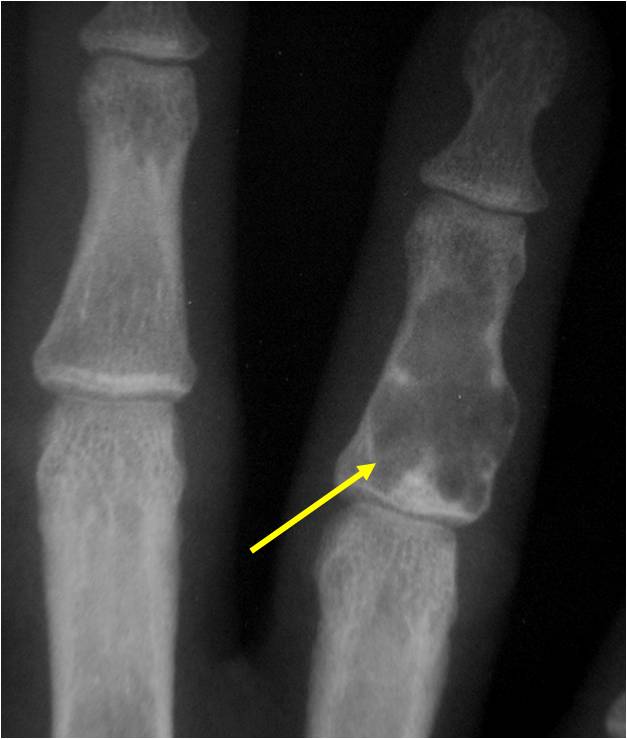

Radiographic Presentation

- Localized, radiolucent defect usually with punctate calcifications

- Calcifications are typical but not always present

- Matrix may demonstrate various degrees of calcification

- Calcifications are stippled, punctate, popcorn like calcifications and “Ring and Arc” calcifications

- Cartilage tumors grow in a lobular manner. The perimeters of the lobules undergo

- enchondral ossification that may calcify. If the entire perimeter of the lobule calcifies it appears

- radiographically as a “Ring”. If a portion of the perimeter of a lobule calcifies it forms an “Arc” on

- an X-ray.

- May be located centrally or eccentrically

- Grows eccentrically or concentrically (phalanges)

- Cortex may be scalloped and thinned in the phalanges

Plain X-Ray:

- Geographic lytic lesion

- Central often metaphyseal in long bones

- Can be eccentric also

- Expansile remodeling with thinned cortex

- Chondroid matrix with calcifications in majority of tumors

- Approximately 20% have limited or no calcifications